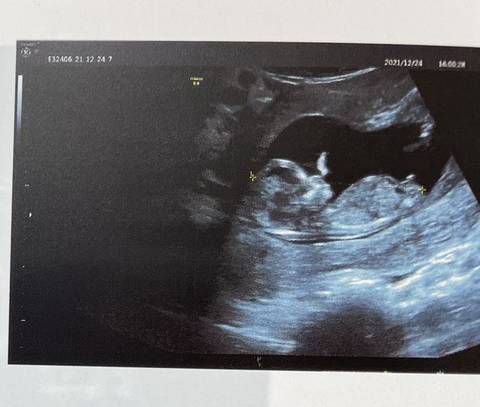

集美们,帮我看看是公主还是王子呀,好多集美看NT能看得出,我愣是没看懂啥????

你好。我们是判断不了男宝宝跟女宝宝的,孕期定期检查,我觉得宝宝健康就好的。祝心想事成 。